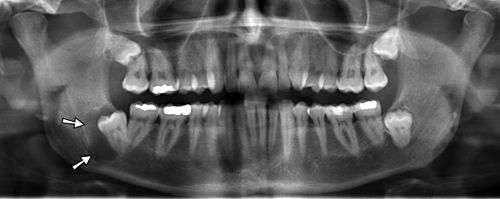

Panoramic radiographs have the capability to demonstrate a portion of the neck and display atheromas (calcifications in the carotid artery) which are an indication of both local and generalized (systemic) atherosclerosis. Atherosclerosis of the coronary arteries leading to myocardial infarction (heart attack), and atherosclerosis of the carotid artery leading to stroke are the number one and number three most common causes of death in the United States.[5]

Epidemiology: General Public and High Risk Groups

Additional research projects have further determined the prevalence rate of these atheromas in the general population (3-5%)[7] and among high-risk groups (over 25% in: recent stroke victims,[8] individuals with obstructive sleep apnea syndrome,[9][10] postmenopausal women,[11] type 2 diabetics,[12][13] individuals with dilated cardiomyopathy,[14] and among individuals who have received radiotherapy directed at the neck,[15][16]). These findings have been corroborated by other several other researchers.[17][18][19][20]

Atherosclerosis is attributed to risk factors that include cigarette smoking, hyperlipidemia, obesity, diabetes mellitus, and hypertension (high blood pressure). These factors, however, do not fully account for the risk of disease. Atherosclerosis has been conceptualized as a chronic inflammatory response to endothelial cell injury[21] and dysfunction possibly arising from chronic dental infection. In 2010, using the previously validated Mattila panoramic radiographic index to quantify the totality of dental infection (i.e., periapical and furcal lesions, pericoronitis sites, carious tooth roots, teeth with pulpal caries, and vertical bony defects), Friedlander’s group determined that individuals with carotid artery atheromas on their panoramic radiographs had significantly greater amounts of dental infection/inflammation than atherogenic risk-matched controls devoid of radiographic atheromas.[22][23] While the Mattila index had been previously used to relate the extent of dental infection to coronary artery disease, this research is the first to link the full range of dental disease that it measures to panoramic radiographs evidencing calcified carotid artery atherosclerosis.